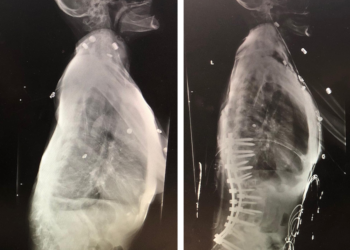

Back:

Revision Surgery Treats Intractable Neck Pain & Cervical Deformity

Author: Benjamin R. Cohen M.D., F.A.A.N.S., F.A.C.S., Read More!